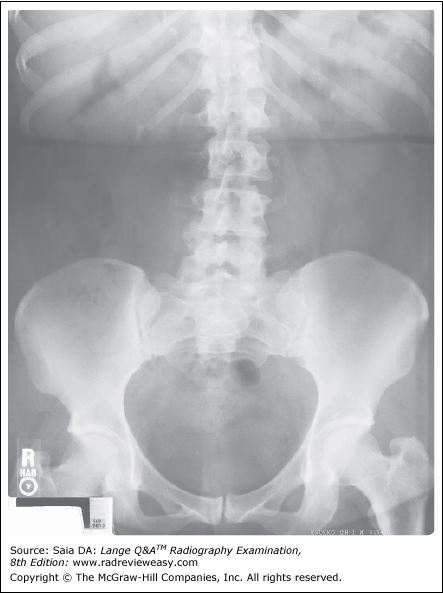

What is the correct critique of the CR image shown in Figure 4–3?

A double exposure

B inverted IP

C incomplete erasure

D image fading

-The image shown is a double exposure. Note the ilia and lower pelvic structures. Two pelves are clearly identifiable. Particularly noteworthy is how CR will “correct” the exposure values. The image does not appear overexposed, but the superimposed abdominal images are unmistakably evident. An inverted IP would have imaged the rear panel of the IP—a large grid-like appearance. An incomplete erasure or image fading would show only a portion of the image—here we have the entire superimposed abdomen.